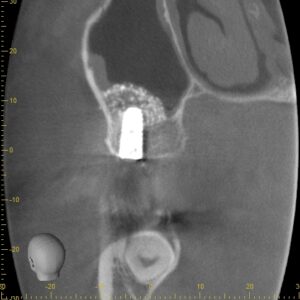

本日は、ラテラルスリット法によるサイナスリフトを行いました。